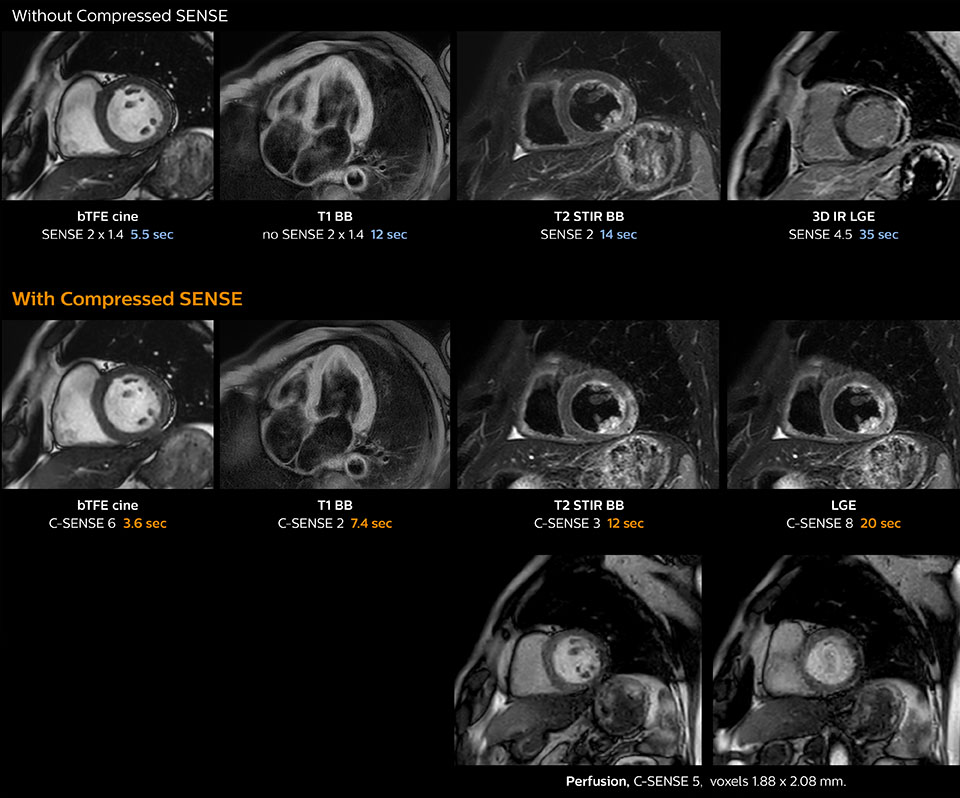

“Compressed SENSE has now been implemented in all cardiac exams. Thanks to the acceleration, fewer breath holds are now needed, or breath hold times are shortened. This reduces the burden of the exam for cardiac patients, without affecting the quality of information required for cardiac function analyses,” he says. “Because it’s easier for patients to comply with the breath hold times” “In our previous cardiac cine sequence, we were acquiring two slices during one breath hold. With Compressed SENSE, we increased this to four slices per breath hold. It is also possible to shorten scanning time using a C-SENSE factor 6 without sacrificing image quality.”

Dr. Koshi Miyake, cardiologist, explains that scanning of patients with cardiac arrhythmia can be challenging, as scanning times can become very long due to the varying heart rate. So his most important motive to implement Compressed SENSE in cardiac MRI exams was to reduce the burden of breath holds for the patient, while maintaining high image quality. He hopes this can also help to reduce motion caused by the difficulty for patients to hold their breath.

“Typically, in scans with high contrast, such as 2D balanced TFE cine, a quite high C-SENSE factor may be used. When we tried a higher C-SENSE factor, we saw still no significant influence on cardiac ejection fraction, but 2D image quality started to decline. For coronary imaging, we use a C-SENSE factor of 3 in 3D balanced TFE, or even up to 4 when contrast is high.”

These images of a patient with acute myocardial infarction images were acquired on Ingenia 1.5T with and without Compressed SENSE.